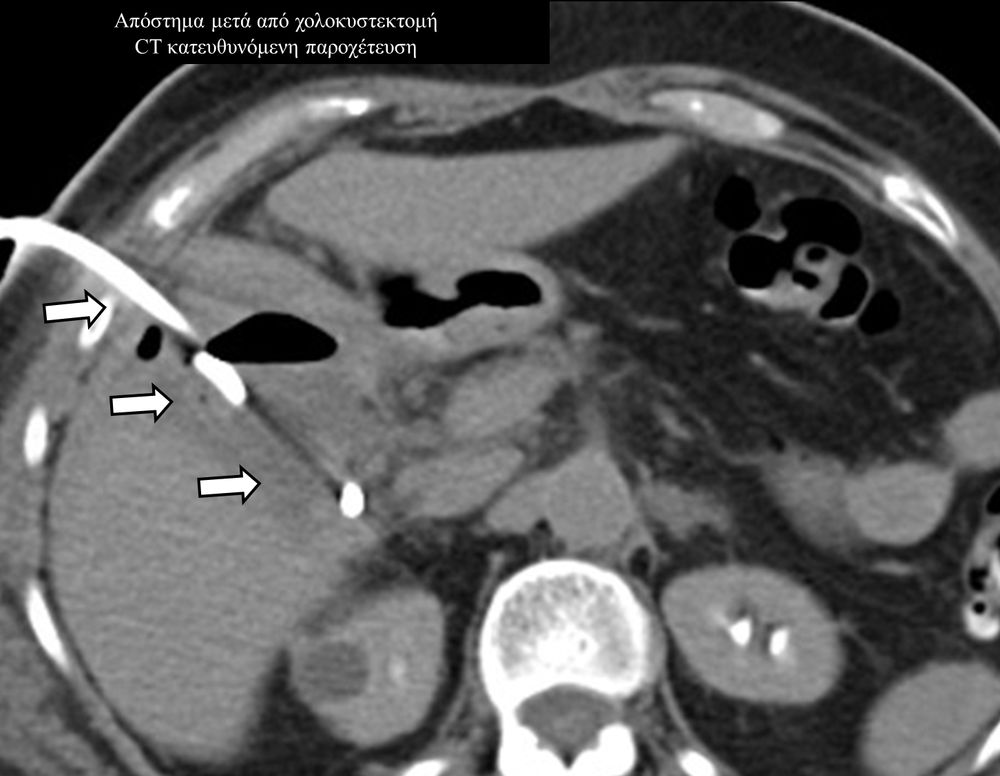

Οι απεικονιστικά καθοδηγούμενες διαδερμικές παροχετεύσεις είναι ελάχιστα επεμβατικές μέθοδοι εξωτερικής παροχέτευσης συμπτωματικών συλλογών, όπως ασκιτικές-καρκινικές-μετεγχειρητικές συλλογές, αποστήματα, πλευριτικές συλλογές-εμπυήματα.

Η παρέμβαση διενεργείται υπό την καθοδήγηση αξονικού τομογράφου ή υπερήχων ή και με συνδυασμό τους. Ο επεμβατικός ακτινολόγος αρχικά αναισθητοποιεί την ανατομική περιοχή ενδιαφέροντος με τη χρήση τοπικής αναισθησίας και παρακεντεί την συλλογή διαδερμικά με λεπτή βελόνη. Στη συνέχεια μέσω ομοαξονικών συστημάτων συρμάτων-καθετήρων-διαστολέωντοποθετείται διαδερμικός καθετήρας τύπου pig-tail εντός της συλλογής, ο οποίος συνδέεται με εξωτερική παροχέτευση.